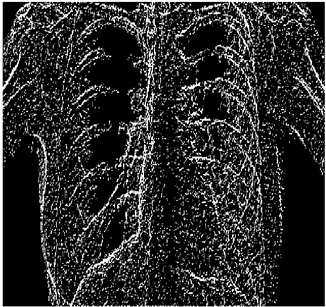

5. Results and Discussions

For the purpose of simulation, we consider two sets of images: (1) three images from MATLAB repository (Table 4) and (2) five X-ray images available online (Table 5).

As shown in Table 6, the PFOM values related to the smooth composition are higher than those of the standard composition in all cases. Table 7, Table 8, Table 9, Table 10, Table 11, Table 12, Table 13 and Table 14 also provide a visual demonstration supporting this conclusion. As is quite obvious from these tables, the density of noise in the edge-detected images of smooth composition is always less than that of the standard composition. Furthermore, the Canny edge detector is also highly prone to noises and is unable to decrease the noise density.

Table 10 shows the following:

• In all cases, the Canny edge detector detects more edge pixels than both fuzzy compositions.

• As the level of noise increases, Canny and standard composition become adversely affected by the noise, and still more edges are detected by Canny; however, most of the detected edges by Canny are misdetections due to the impact of noise. As is obvious from this table, the smooth composition provides a better image with reduced noise density.

• In all cases, the PFOM value for the smooth composition is always greater than the PFOM value for the standard composition, according to Table 6.

Table 10. Edge-detected image of “X-ray 1” after binarization for different noises.

NoiseCannyStandardSmooth

No noise Mathematics 10 02421 i072 Mathematics 10 02421 i073 Mathematics 10 02421 i074

G(0.001) Mathematics 10 02421 i075 Mathematics 10 02421 i076 Mathematics 10 02421 i077

G(0.002) Mathematics 10 02421 i078 Mathematics 10 02421 i079 Mathematics 10 02421 i080

G(0.003) Mathematics 10 02421 i081 Mathematics 10 02421 i082 Mathematics 10 02421 i083

I(0.25%) Mathematics 10 02421 i084 Mathematics 10 02421 i085 Mathematics 10 02421 i086

I(0.5%) Mathematics 10 02421 i087 Mathematics 10 02421 i088 Mathematics 10 02421 i089

I(1%) Mathematics 10 02421 i090 Mathematics 10 02421 i091 Mathematics 10 02421 i092